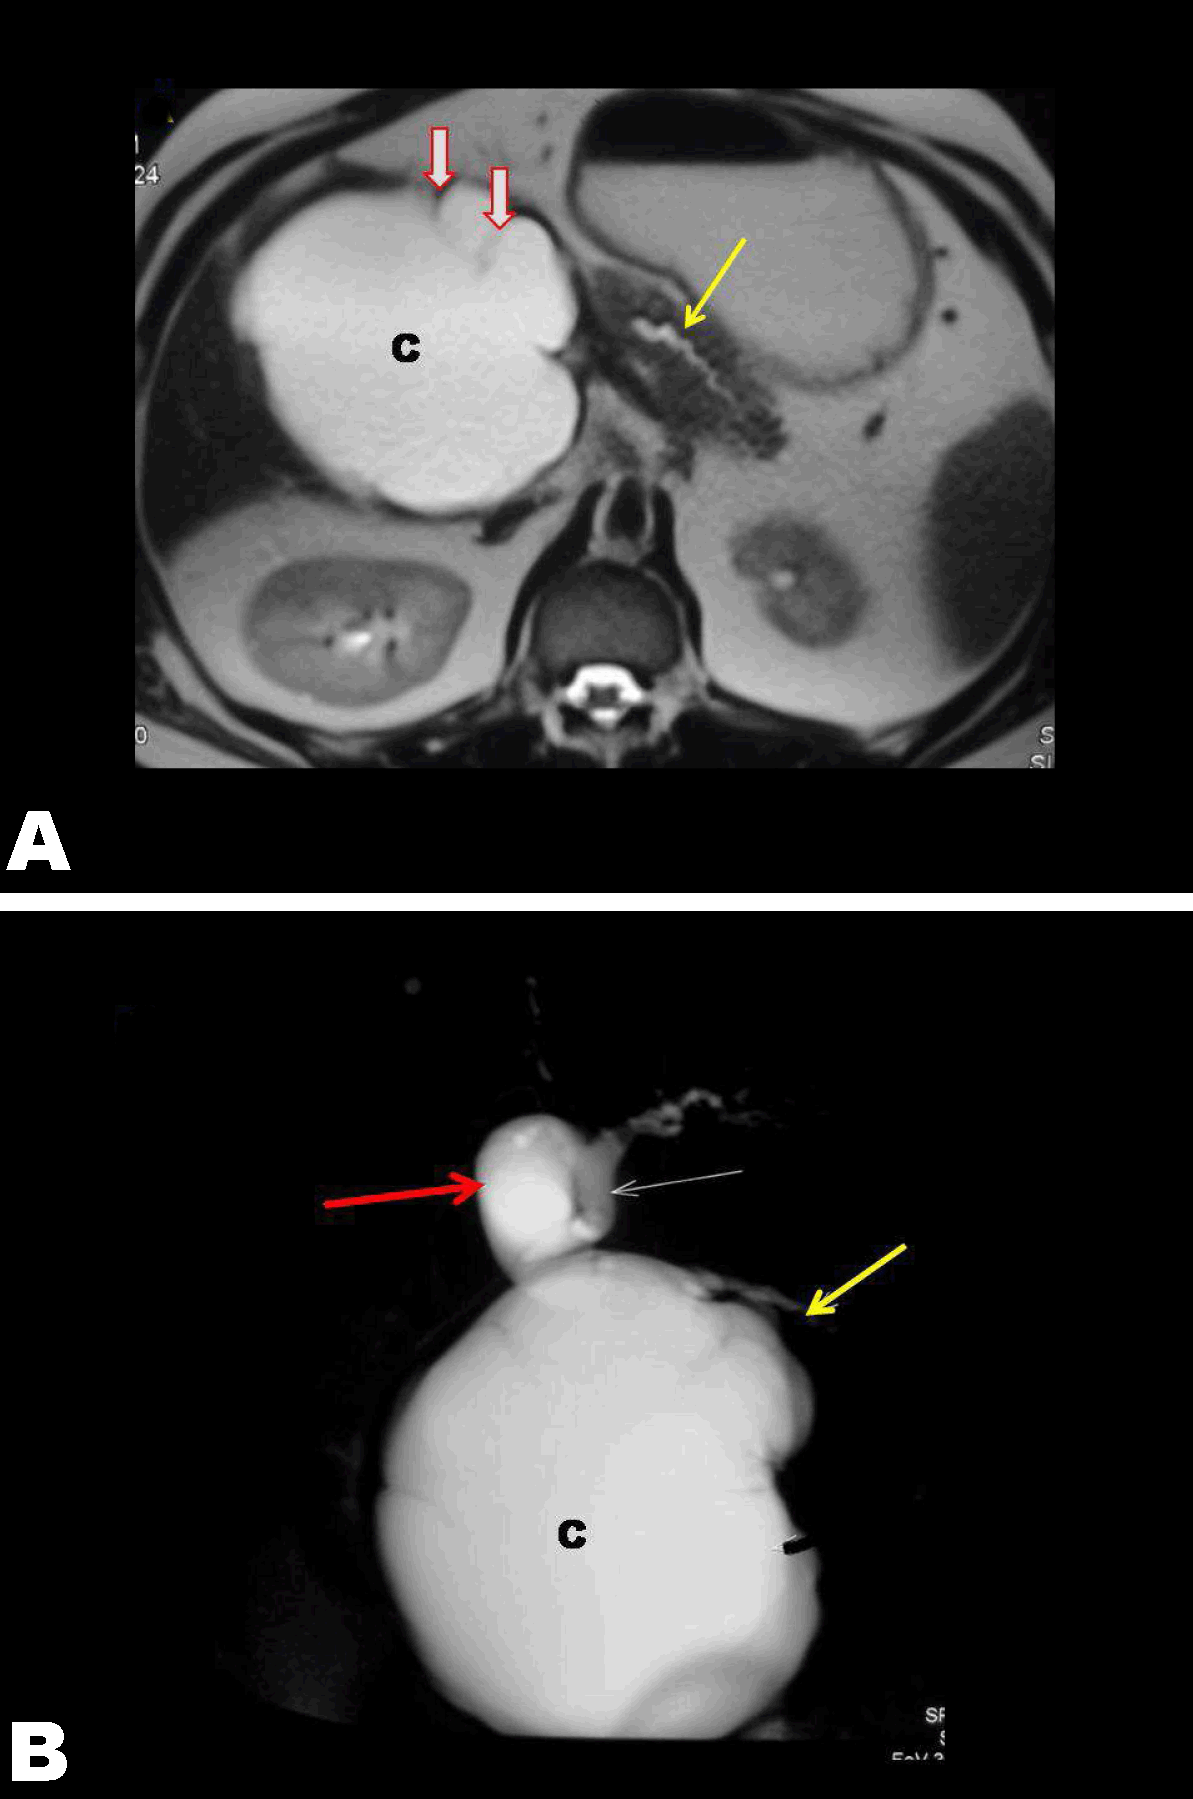

A 41-year-old male patient with borderline hypertension, presented to us with complaints of jaundice and postprandial vomiting started one and a half months before without any fever or alteration of bowel, bladder habit. But he noticed a spontaneous partial relief of his symptoms for 10–15 days before he presented to us. Though he has some loss of appetite and weight, but his performance status was otherwise good. At the time of admission patient was icteric with serum bilirubin of 3.5 mg/dL, alkaline phosphate 1414 U/l and GGTP 474 U/l. Physical examination revealed a large firm mass present in upper abdomen extending from right hypochondrium, epigastrium to right lumber and umbilical region. It was non-tender, partially fixed, and dull on percussion without any abnormal pulsation. Contrast computed tomography (CT) scan revealed a well-defined unilocular cyst measuring 15.2x12.1x11.6 cm arising from the head of pancreas pressing over the duodenum and common bile duct (CBD) with dilatation of main pancreatic duct (MPD) (Figure 1). Magnetic resonance cholangiopancreatography (MRCP) revealed dilated CBD and MPD with communication between the cyst and MPD (Figure 2). Endoscopic ultrasound showed unilocular cyst without further specification. Endoscopic ultrasound guided fine-needle aspiration cytology (FNAC)was done for fluid analyses, biochemistry and cytology. Cytology of cyst fluid did not show any malignant cell, cyst fluid CEA was 1.4 ng/mL. Fluid amylase (60 IU/l) and CA19–9 (14.71 U/mL) were within normal limits. In view of obstructive symptoms due to giant size of the lesion pancreaticoduodenectomy was planned. On exploration a huge unilocular cyst measuring 15 cm in greatest dimension was found, displacing the duodenum and pylorus, superior mesenteric vessels and portal vein. Cyst was densely adhered to anterior surface of right kidney, inferior vena cava (IVC) and portal vein. Pancreaticoduodenectomy was performed with Roux-en-Y reconstruction. Postoperative recovery was uneventful and the patient was discharged on sixth postoperative day. Biopsy revealed a solitary cyst filled with hemorrhagic fluid with maximum wall thickness of 1 cm. Microscopic examination showed a cuboidal epithelial lining of cyst wall with focal papillary formation and multi-layering. Cells showed moderate clear cytoplasm and uniform round nuclei without any pleomorphism or mitosis. Cyst wall showed dense fibrosis and patchy mild chronic inflammatory cell infiltrate. Final histopathological diagnosis was serous oligocystic adenoma head of pancreas. |